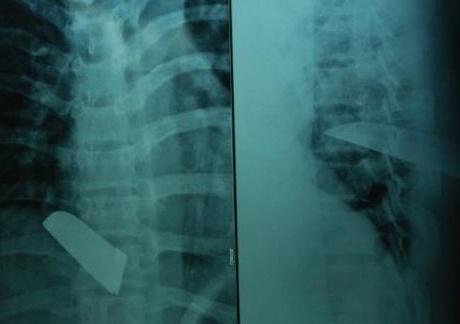

Anh Vũ (Long An) lấy dao tự đâm vào tim, được người nhà phát hiện đưa đi cấp cứu trong tình trạng vết thương thấu ngực sát tim, gây đứt động mạch, cực kỳ nguy hiểm.

Ngày 12/5, bác sĩ Trần Văn Ân, Phó giám đốc Bệnh viện Đa khoa Nguyễn Đình Chiểu (tỉnh Bến Tre), cho biết các bác sĩ bệnh viện vừa cứu sống một nạn nhân bị vật nhọn đâm thủng tim.